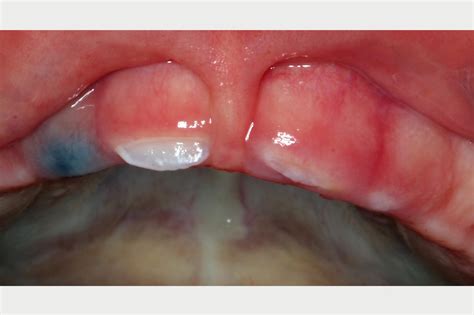

An Eruption Hematoma Cyst is essentially a localized collection of blood trapped within the gingival tissue surrounding an erupting tooth. It is a soft tissue variant of an eruption cyst. When a tooth pushes through the bone and enters the gum tissue, it can rupture small blood vessels in the area. If the blood becomes trapped under the gingival surface before the tooth fully emerges, it creates the characteristic dark, bruised, or blue-purple appearance that defines the condition.

Although the color might lead you to believe that the area is severely damaged, this is generally a natural part of the eruption process. It most commonly occurs in children as they lose their baby teeth and their permanent molars begin to erupt. The physical pressure of the emerging tooth crown against the delicate gum tissue is what triggers the minor bleeding that leads to the hematoma.

Appearance Blue, purple, or deep red dome-shaped swelling.

Location Over the crown of an erupting tooth.

Texture Soft, fluctuant, and sometimes tender to the touch.